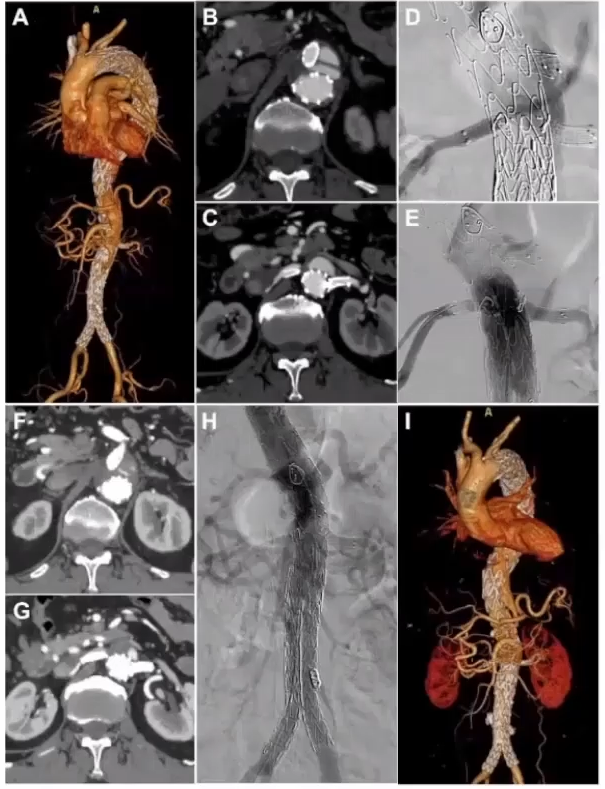

病例分享2

该患者为三期手术,除了第一次在外院手术外,之后在本院行两次手术。在第二期手术时,进行主髂和内脏区四分支重建术。1月后行第三期主髂段手术,此时可以清楚观察到潜在的内漏,并在第三期手术行内漏补救措施。该内漏是由内脏区右肾动脉真假腔供血引起,用Viabahn延长右肾动脉来做覆盖。在近期随访中,内脏区的内漏完全消失了,正好体现第三阶段主髂段进行修补的理念。

三期术后半年随访

6月后,lc型内漏的补救处理

病例分享3

患者男性,63岁,急性胸痛5小时入院。该患者从主动脉弓部直到髂动脉撕裂的 B型夹层,为全程三阶段管理的病例。第一阶段进行降主动脉几乎全程覆盖。在第二阶段真腔狭小,下肢有缺血的表现,行3D打印模型下的F/B EVAR手术。第三阶段在做完主髂段后再做主髂,尽量保髂内动脉重建。采用激光原位技术将双侧髂内动脉全部保留,减少髂内动脉对脊髓缺血的影响。手术中发现出现假腔II型内漏,内漏相对较小可以随访观察。最近随访观察肠系膜下动脉内漏完全消失。